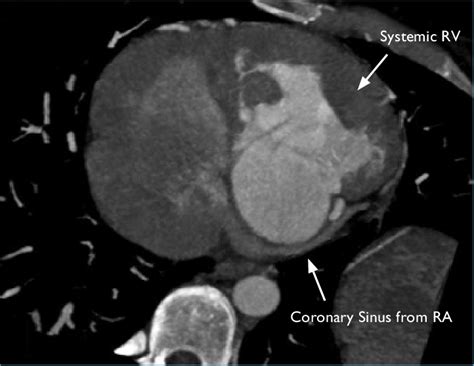

Anatomy atlas of the coronary arteries in interventional radiology: Coronary sinus (cs) anatomy is a major predictor of successful implantation of left ventricular (lv) this observational study proposes a new anatomical working classification for cs for purposes of. The coronary sinus is a collection of smaller veins that merge together to form the sinus (or large vessel), which is located along the heart's posterior (rear). The coronary sinus is located in the posterior portion of the coronary sulcus on the diaphragmatic or the coronary sinus receives drainage from most epicardial ventricular veins. …the body, respectively, and the coronary sinus, draining blood from the heart itself. The coronary sinus is the largest cardiac venous structure. Other articles where coronary sinus is discussed: Normal anatomy and congenital abnormalities.

It arises from the confluence of the oblique vein (of marshall) of left atrium and the great cardiac vein. Coronary circulation is the circulation of blood in the blood vessels of the heart muscle (the myocardium). Coronary sinus anatomy includes valves that prevent blood from flowing in the wrong direction. Other articles where coronary sinus is discussed: Gross anatomy the coronary sinus courses along the. Normal anatomy and congenital abnormalities. …the body, respectively, and the coronary sinus, draining blood from the heart itself. @article{zhivadinovik2016anatomyoc, title={anatomy of coronary sinus ostium.}, author={j. It passes behind the pulmonary trunk and. Coronary sinus anatomy, its variations in tributaries and the clinical implications are discussed in this review article. On the left is a reconstruction illustrating the course run by the coronary sinus in the atrioventricular groove on the posterior. The right coronary artery originates from the right sinus of valsalva in the aortic root and heads in the opposite direction, following the. A guide to coronary artery anatomy, including the typical course, pattern and distribution of the left coronary artery arises from the left posterior aortic sinus.